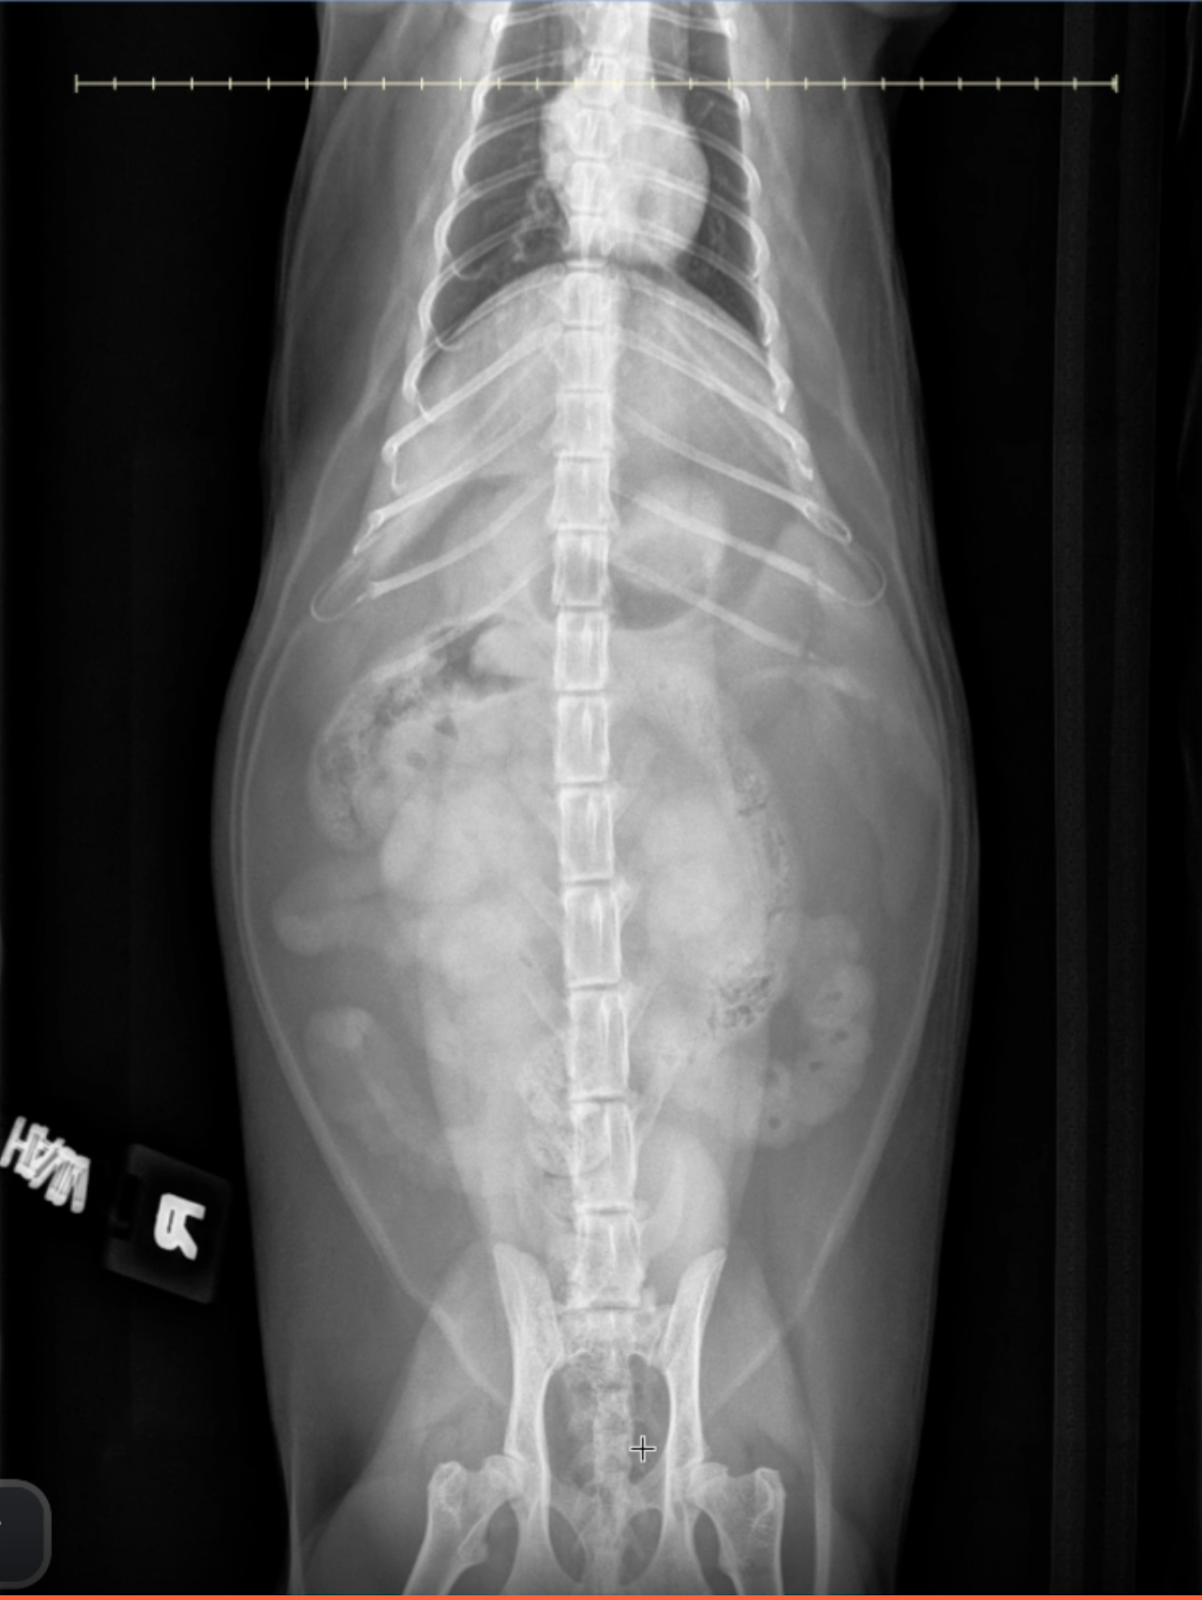

VD abdominal radiograph of a cat with serpentine, radiating plicated small intestines and fragmented gas pattern, diagnostic for LFBO.

Image 3: Ventrodorsal (VD) View

• Loop Orientation: Plicated loops are centrally displaced, often forming radiating, serpentine patterns.

• No foreign body is directly visualized, but the overall pattern confirms functional obstruction.